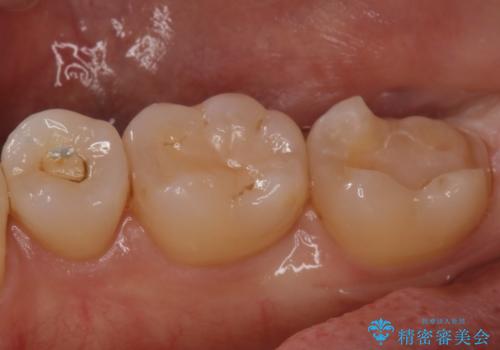

- 昔に治療した金属のかぶせものが取れてしまい来院されました。他院にて応急処置がされており、レントゲンなどで現状を把握した後、切削量が比較的少なく短期間で終了するセラミックアンレーにて治療いたしました。

経過良好で噛み合わせなども問題なく、前の被せ物より綺麗な被せ物がセットされ、非常に満足いただけました。